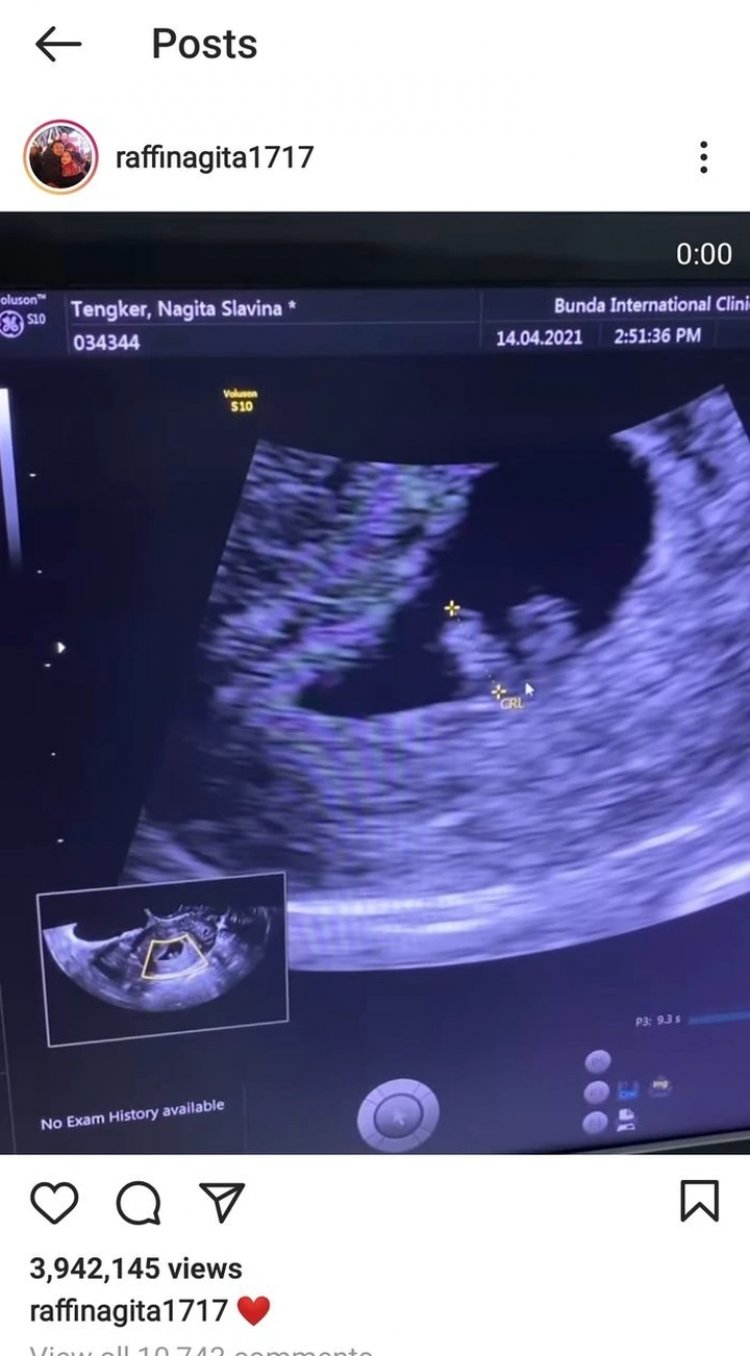

Dalam video dua detik di Instagram @raffinagita1717, terlihat nama lengkap Nagita Slavina yang tes USG di salah satu rumah sakit Jakarta, Rabu (14/4/2021).

Hasil USG Nagita Slavina. (Instagram @raffinagita1717)